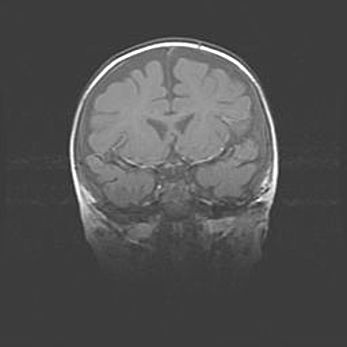

Открытая гидроцефалия.

Возраст: 9 месяцев 12 дней

Вес: 6800 г

Пол: мужской

Окружность головы: 41,5 см

Срок гестации: 28 недель

Гидроцефалия головного мозга у новорожденных имеет характерный признак: опережающий рост окружности головы приводит к визуально хорошо определяемой гидроцефальной форме сильно увеличенного в объёме черепа. Детские неврологи определяют следующие симптомы гидроцефалии у грудничков: выбухающий напряжённый родничок, частое запрокидывание головы, смещение глазных яблок к низу.